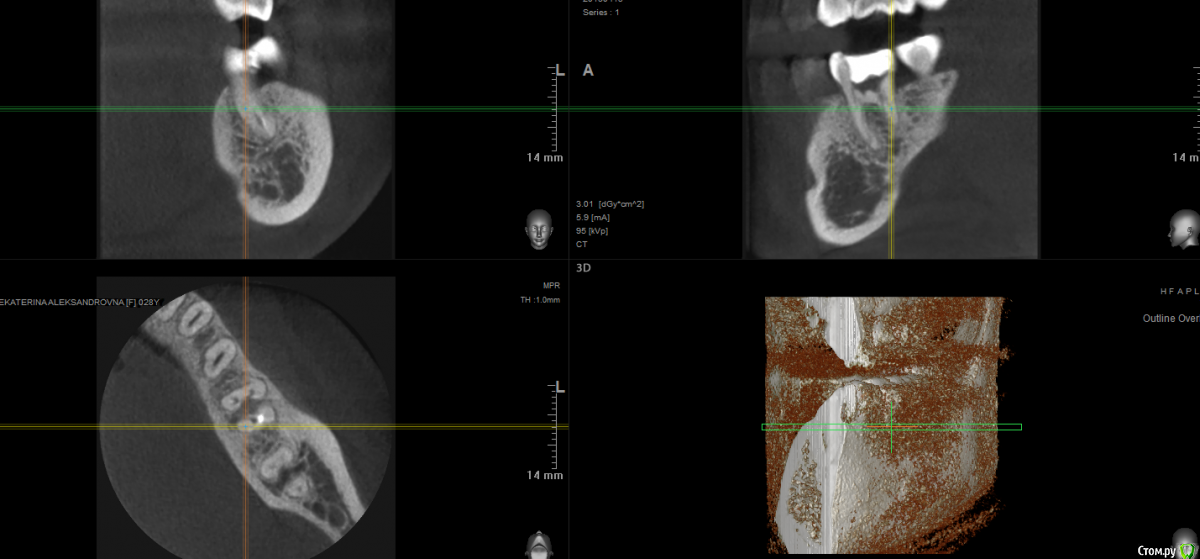

В общем, сходила я в другую клинику, сделали рентген, посмотрели, выписали антибиотики, дали месяц зубу, коронку на него нельзя, и по их словам даже если выживет, то около года протянет. На сегодняшний день, изменения не особо: в определенном смыкании боль осталась, бывает даже от прикосновения к зубу, не сильная, либо я за полгода лечения привыкла к ней. На днях сделала 3д снимок, хотелось бы узнать мнение профи: делать имплант, одноэтапный? надо наращивать кость? или всё же ещё раз перелечить зуб?

post-57643-0-17270100-1555936949_thumb.png